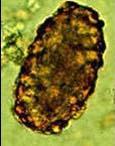

问题 下图是哪一寄生虫卵 ( )

选项 A、钩虫卵 B、鞭虫卵 C、未受精的蛔虫卵 D、蛲虫卵 E、受精的蛔虫卵

答案 C